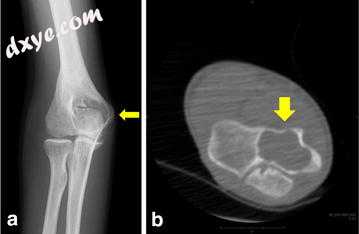

右肘的平片和计算机断层扫描(CT)显示肱骨远端前部有扇形(图1a-c)。磁共振成像(MRI)显示肘关节前部有多个软质量为3×2×2 cm。在T1加权MRI上,病变与肌肉呈等信号(图2a),T2加权成像时主要为高信号,肘关节后关节有液体渗出(图2b)。后钆序列显示厚,外周和间隔增强,这不仅对于肿块而且对整个肘关节都是明显的(图2c)。色素性绒毛结节性滑膜炎,局限性结节性滑膜炎和复杂神经节被认为可能是鉴别诊断。然而,不能排除软组织肉瘤的可能性。在局部麻醉下进行切口活检,组织学检查发现肘关节有结节性筋膜炎。

图1

入院时的平片和计算机断层扫描(CT)结果。 右肘的平片(a),轴向CT(b)和矢状CT(c)显示肱骨远端前部的扇形(黄色箭头)。